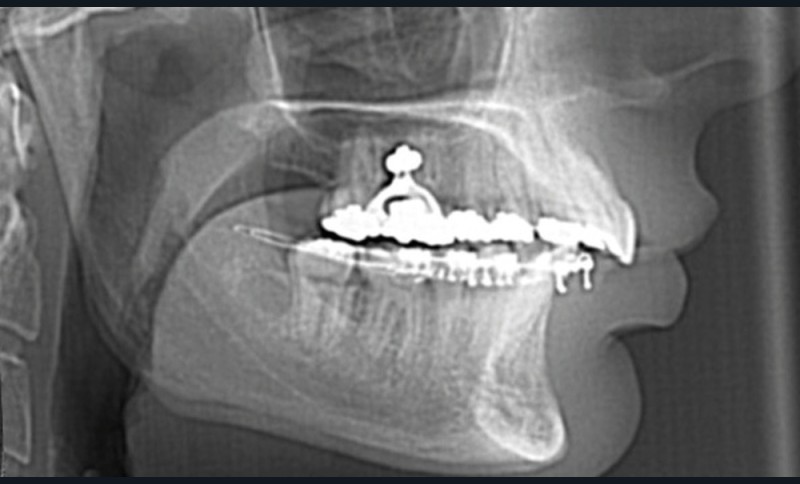

Le Dr Laïla Hitmi poursuivra dans le domaine des nouvelles technologies, en présentant l’ensemble des étapes d’un collage indirect, entièrement numérique : empreinte numérique et alignement avec le cone beam, positionnement virtuel des attaches orthodontiques, confection numérique et impression de la gouttière, transfert clinique.

Le Dr Paul Cresseaux présentera dans un premier temps un ancrage squelettique, simple et efficace, développé par ses soins, pour optimiser la préparation orthodontique des classes II squelettiques : l’Abalakov (fig. 13a-d). Puis, il défendra la prise en charge simultanée, au cours d’un unique temps chirurgical, de l’ensemble des anomalies squelettiques présentées par nos patients.